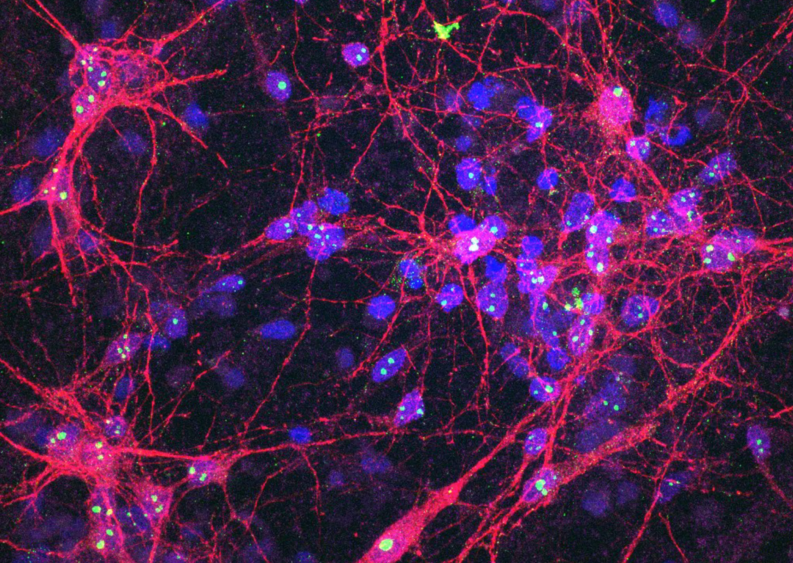

Платформа SBI меняет подход: она использует нейроны, выращенные из индуцированных плюрипотентных стволовых клеток человека (hiPSC). Эти клетки способны превращаться в любые типы клеток организма. Поместив нейроны на кремниевую платформу, ученые получили нейросети, которые могут воспринимать сигналы и отвечать на них в реальном времени, имитируя поведение мозга.

Система, получившая название DishBrain, содержит около 800 000 нейронов человека и мыши, выращенных в лаборатории. Они размещены на массиве электродов, соединенных с компьютером, который запускает упрощенную версию игры Pong — виртуального пинг-понга. Нейроны получают электрические сигналы (например, координаты мяча) и в ответ активизируются, обучаясь через процесс нейропластичности — естественную способность мозга формировать новые связи.

В рамках эксперимента в нейронах искусственно вызвали состояние, похожее на эпилепсию. Для этого применили метод глутаматергической дисрегуляции — нарушения баланса возбуждающего нейромедиатора глутамата, приводящего к чрезмерной активности нейронов.